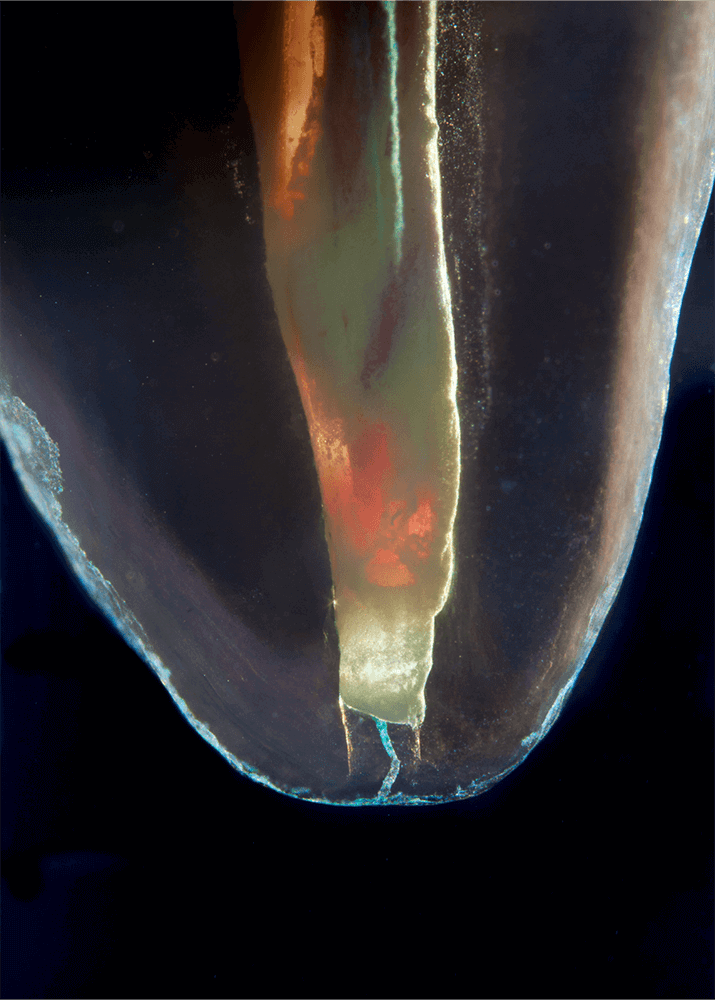

CLEARINGSERVICE bietet Ihnen die Möglichkeit, wurzelgefüllte Zähne mit der Technik des Transparentmachens untersuchen zu lassen. Das geht sehr einfach: Sie schicken uns den zu untersuchenden Zahn, dieser wird dann in ein transparentes Präparat überführt und mit hochwertiger Makrofotografie ausgewertet. Anschließend bekommen Sie die angefertigten Präparate zusammen mit der Fotodokumentation zugeschickt.

Die Bilder sind in verschiedenen Größen wählbar und auch als POPART-Variante erhältlich. Sie sind hervorragend geeignet für die Beratung von Patienten vor endodontischen Behandlungen, aber auch ein beliebter Eyecatcher im Wartezimmer. Außerdem haben die Bilder einen bedeutenden Stellenwert für die Erforschung der Pulpatopografie und für die Lehre im Bereich der Endodontie.